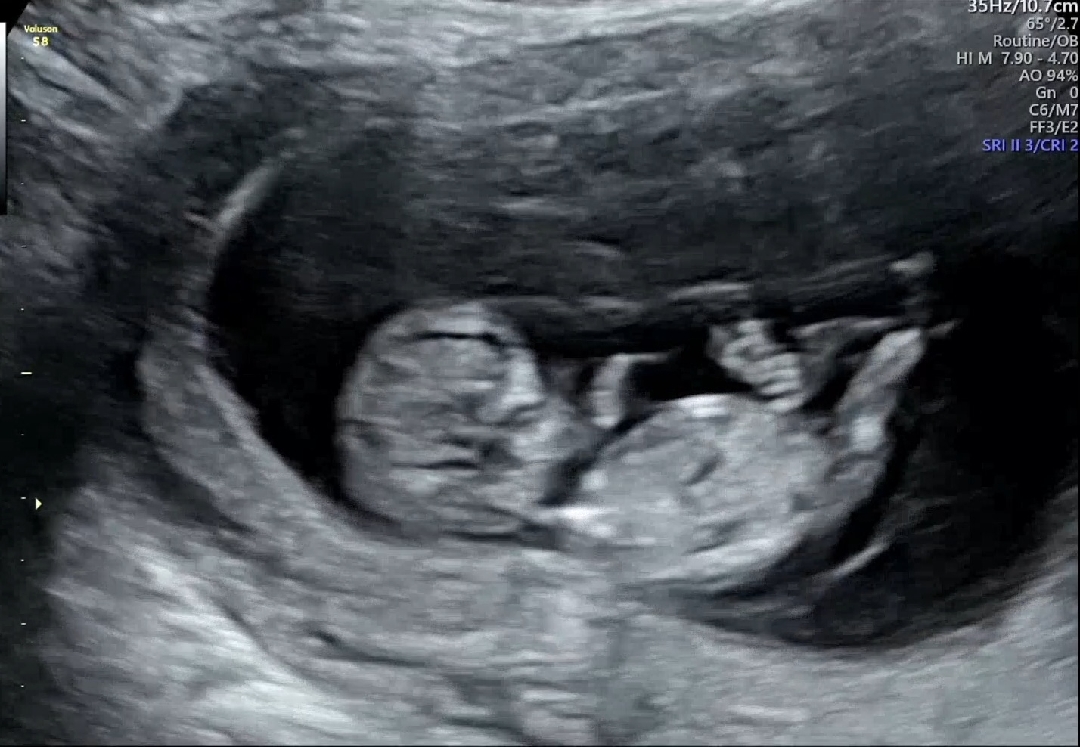

11주0일차 태아성별확인되시나영~?

궁금해서올려봐여

저도 11주1일이라 오늘 초음파 보면서 물어봤는데 ㅋㅋㅋ 아직은 모르죠 그러시더라고요....